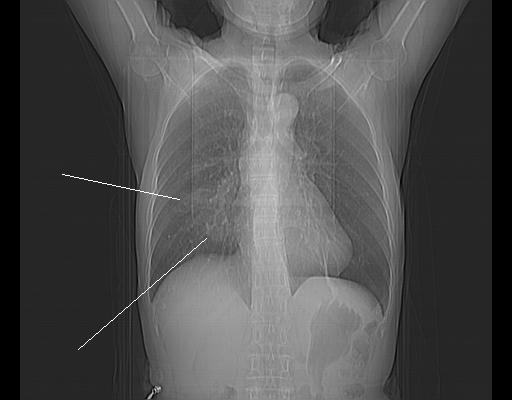

CT50258:女73岁,后背疼痛3天

女73岁,后背疼痛3天,无咳嗽、咳痰,无发热。24552

右中叶支气管狭窄,肺不张,淋巴结钙化,做支气管镜检查确诊。